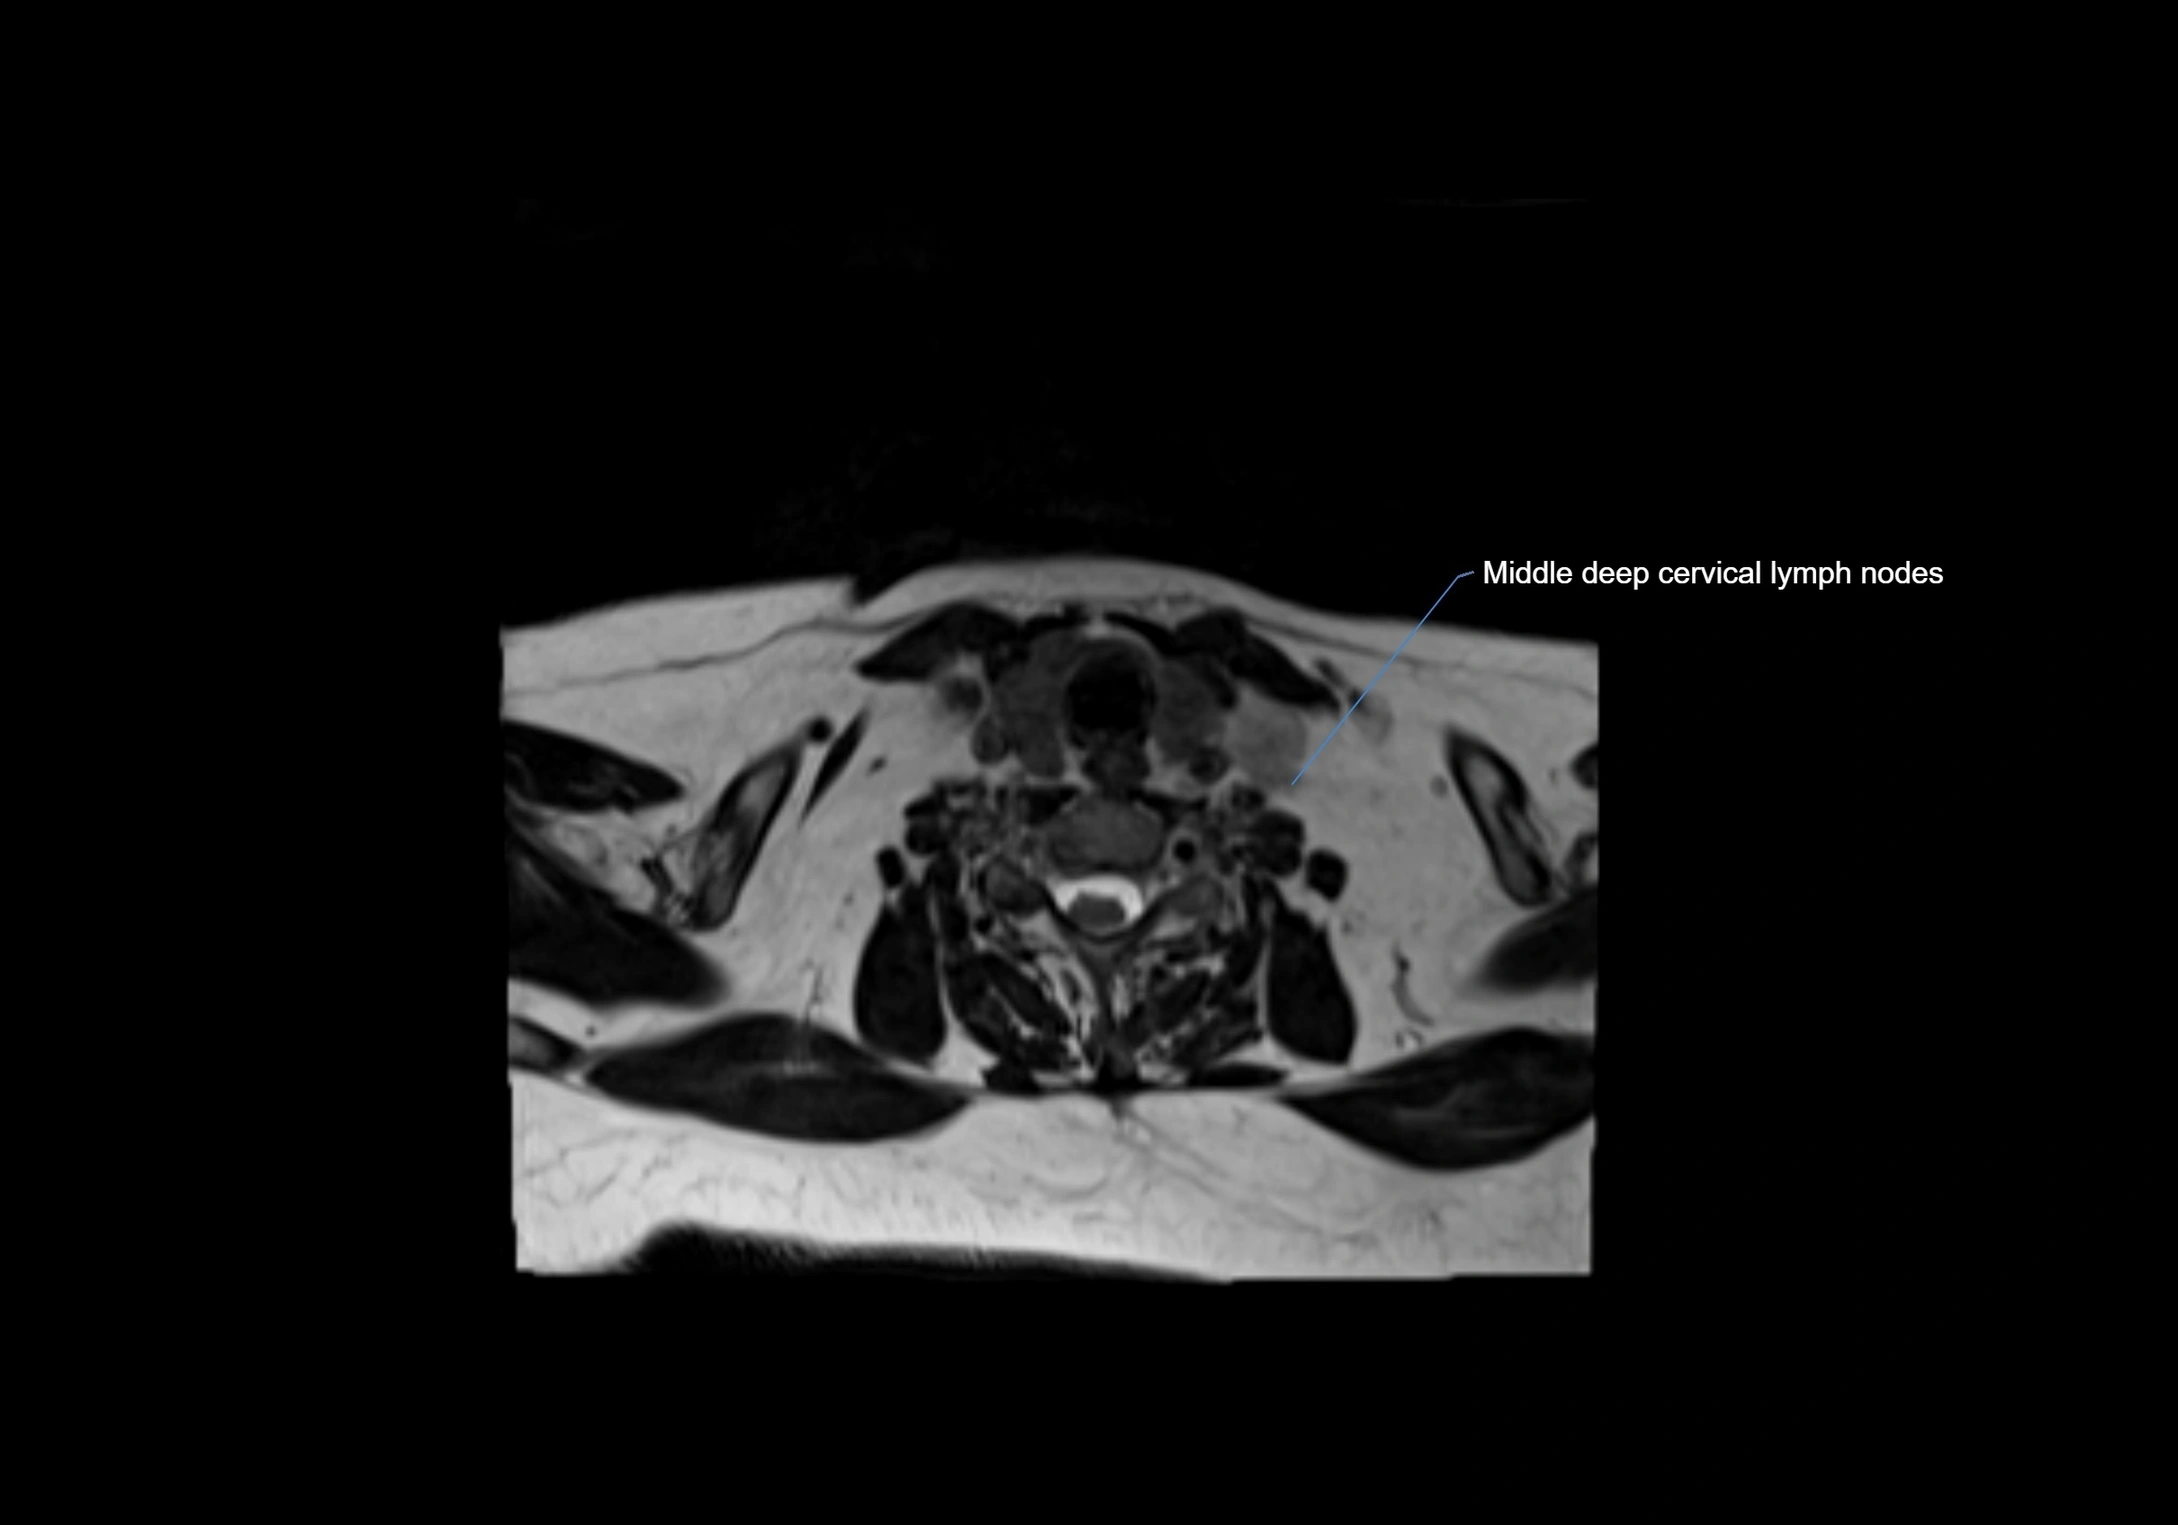

MRI Appearance

T1-weighted images:

• Normal accessory nodes appear as small, oval hypointense to intermediate signal structures within subcutaneous fat

• Surrounded by hyperintense fat, enhancing contrast for visualization

• Pathological nodes may appear enlarged or rounded, sometimes with cortical thickening

T2-weighted images:

• Nodes show intermediate signal, with surrounding fat bright

• Useful for detecting edema, inflammation, or infiltration

• Fatty hilum may appear slightly hyperintense relative to cortex

CT Appearance:

• Nodes appear as small, soft tissue density structures embedded in subcutaneous fat near primary lymph nodes

• Surrounded by air in adjacent facial cavities or normal soft tissue, providing natural contrast

• Enlarged or pathological nodes appear as well-defined or irregular soft tissue masses

• CT is particularly useful for preoperative assessment, infection evaluation, or detection of metastatic spread

MRI images